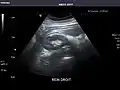

Renal ultrasonography

Ultrasound scan of a kidney (right side)

Ultrasonography of the kidneys is essential in the diagnosis and management of kidney-related diseases. The kidneys are easily examined, and most pathological changes in the kidneys are distinguishable with ultrasound.[7]